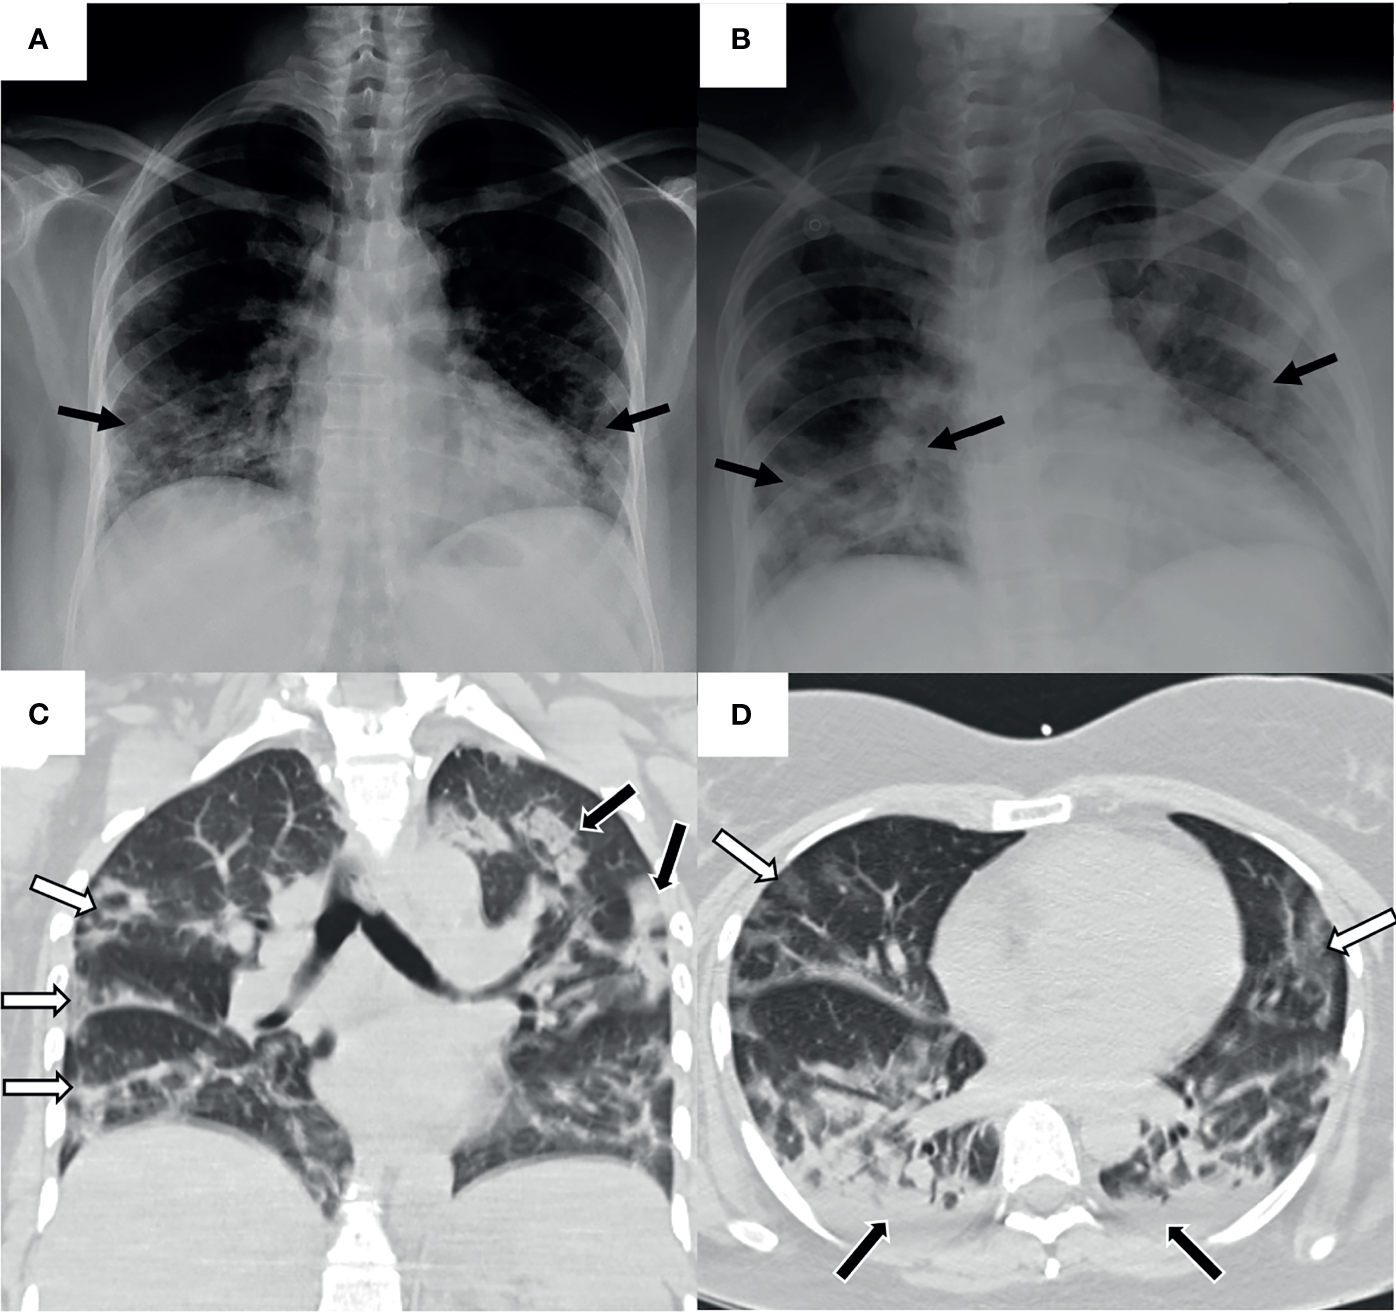

A 44-year-old female patient from, province of Veraguas, in central Panama, presenting with obesity, yet without other pathological antecedents. On March 8, 2020, the patient reported gastrointestinal symptoms (vomit and diarrhea) accompanied by unquantified fever of 9 days of evolution (Figure 1). After visiting the emergency room of the secondary care hospital (Ezequiel Abadia Hospital), the patient received symptomatic outpatient treatment. On March 10, 2020, urinalysis presented with leukocyturia and bacteriuria; she was diagnosed with a urinary tract infection, managed with ciprofloxacin, acetaminophen, and recommendations for outpatient care. Two days later, on March 12, due to the persistence of the symptoms, the patient was admitted to the same hospital for observation. Chest radiography, hematology test, and Dengue virus serology test were performed with no relevant findings. On March 13, the patient presented stable vital signs, temperature (T)=36.8°C, blood pressure (BP)=121/81 mmHg, heart rate (HR)=96 bpm and respiration rate (RR)=18 rpm. Eight hours later, the patient started a persistent cough, tachypnea (RR=36 rpm), and arterial oxygen saturation of SaO2=93% (Table 1). The posteroanterior chest radiography showed a mild peripheral diffuse infiltrate with predominance in both pulmonary bases (Figure 2A). Wherefore, oxygen therapy with nasal cannula was started early in the morning on March 14. The same day in the evening, the anteroposterior chest radiography showed an increased extent of the infiltrate in both pulmonary fields (Figure 2B), with worsening clinical conditions. The arterial gasometry showed SaO2=96%, arterial partial pressure of oxygen (pO2)=72 mmHg and standard bicarbonate (sHCO3)=23.9 mmol/L, arterial partial pressure/fraction of inspired oxygen (PaO2/FiO2)=180. The patient required intubation and mechanical ventilation and was transferred, to the secondary care hospital, Luis “Chicho” Fabrega Hospital. After evaluation by the Pneumology Service in the emergency room, the patient was admitted directly to the intensive care unit (ICU). A high-resolution chest computed tomography reported scattered multifocal opacities of peripheral bilateral predominance with ground glass images, consolidative foci, and scarce bilateral pleural effusion (Figures 2C, D). The patient was hemodynamically compensated with vasopressor support and maintained under sedoanalgesia coupled to mechanical ventilation in assisted-control pressure mode. The patient had feverish peaks that persisted during the following days. The patient presented transaminases slightly increased (AST range: 34-74U/L; ALT range: 30-74U/L). However, she did not present thrombocytopenia (Platelets range: 154-740x103) nor hemoconcentration (Hematocrit range: 24.9-37.2%). Other clinical laboratory analyses showed no relevant findings (Table 1).

Figure 2

Pulmonary images of the patient with HPS and COVID-19. Taken in the intern medicine ward. (A) Posteroanterior chest radiography. Mild peripheral diffuse infiltrate of predominance in both pulmonary bases (black arrows). No cardiomegaly, no pleural effusion. (B) Anteroposterior chest radiography. Increased extent of the radiographic infiltrate in both pulmonary fields (black arrows). No pleural effusion. A rapid progression of the infiltrate is observed in 10 hours of evolution compared to previous radiography. (C) Coronal chest high-resolution simple computed tomography. Scattered multifocal opacities of peripheral predominance in both lungs (white arrows). Isolated consolidated areas (black arrows). (D) Axial chest high-resolution simple computed tomography. Tarnished glass-like opacities in anterior pulmonary location (white arrows) and consolidated areas in posterior pulmonary location (black arrows). Mild bilateral basal posterior pleural effusion (black arrows).